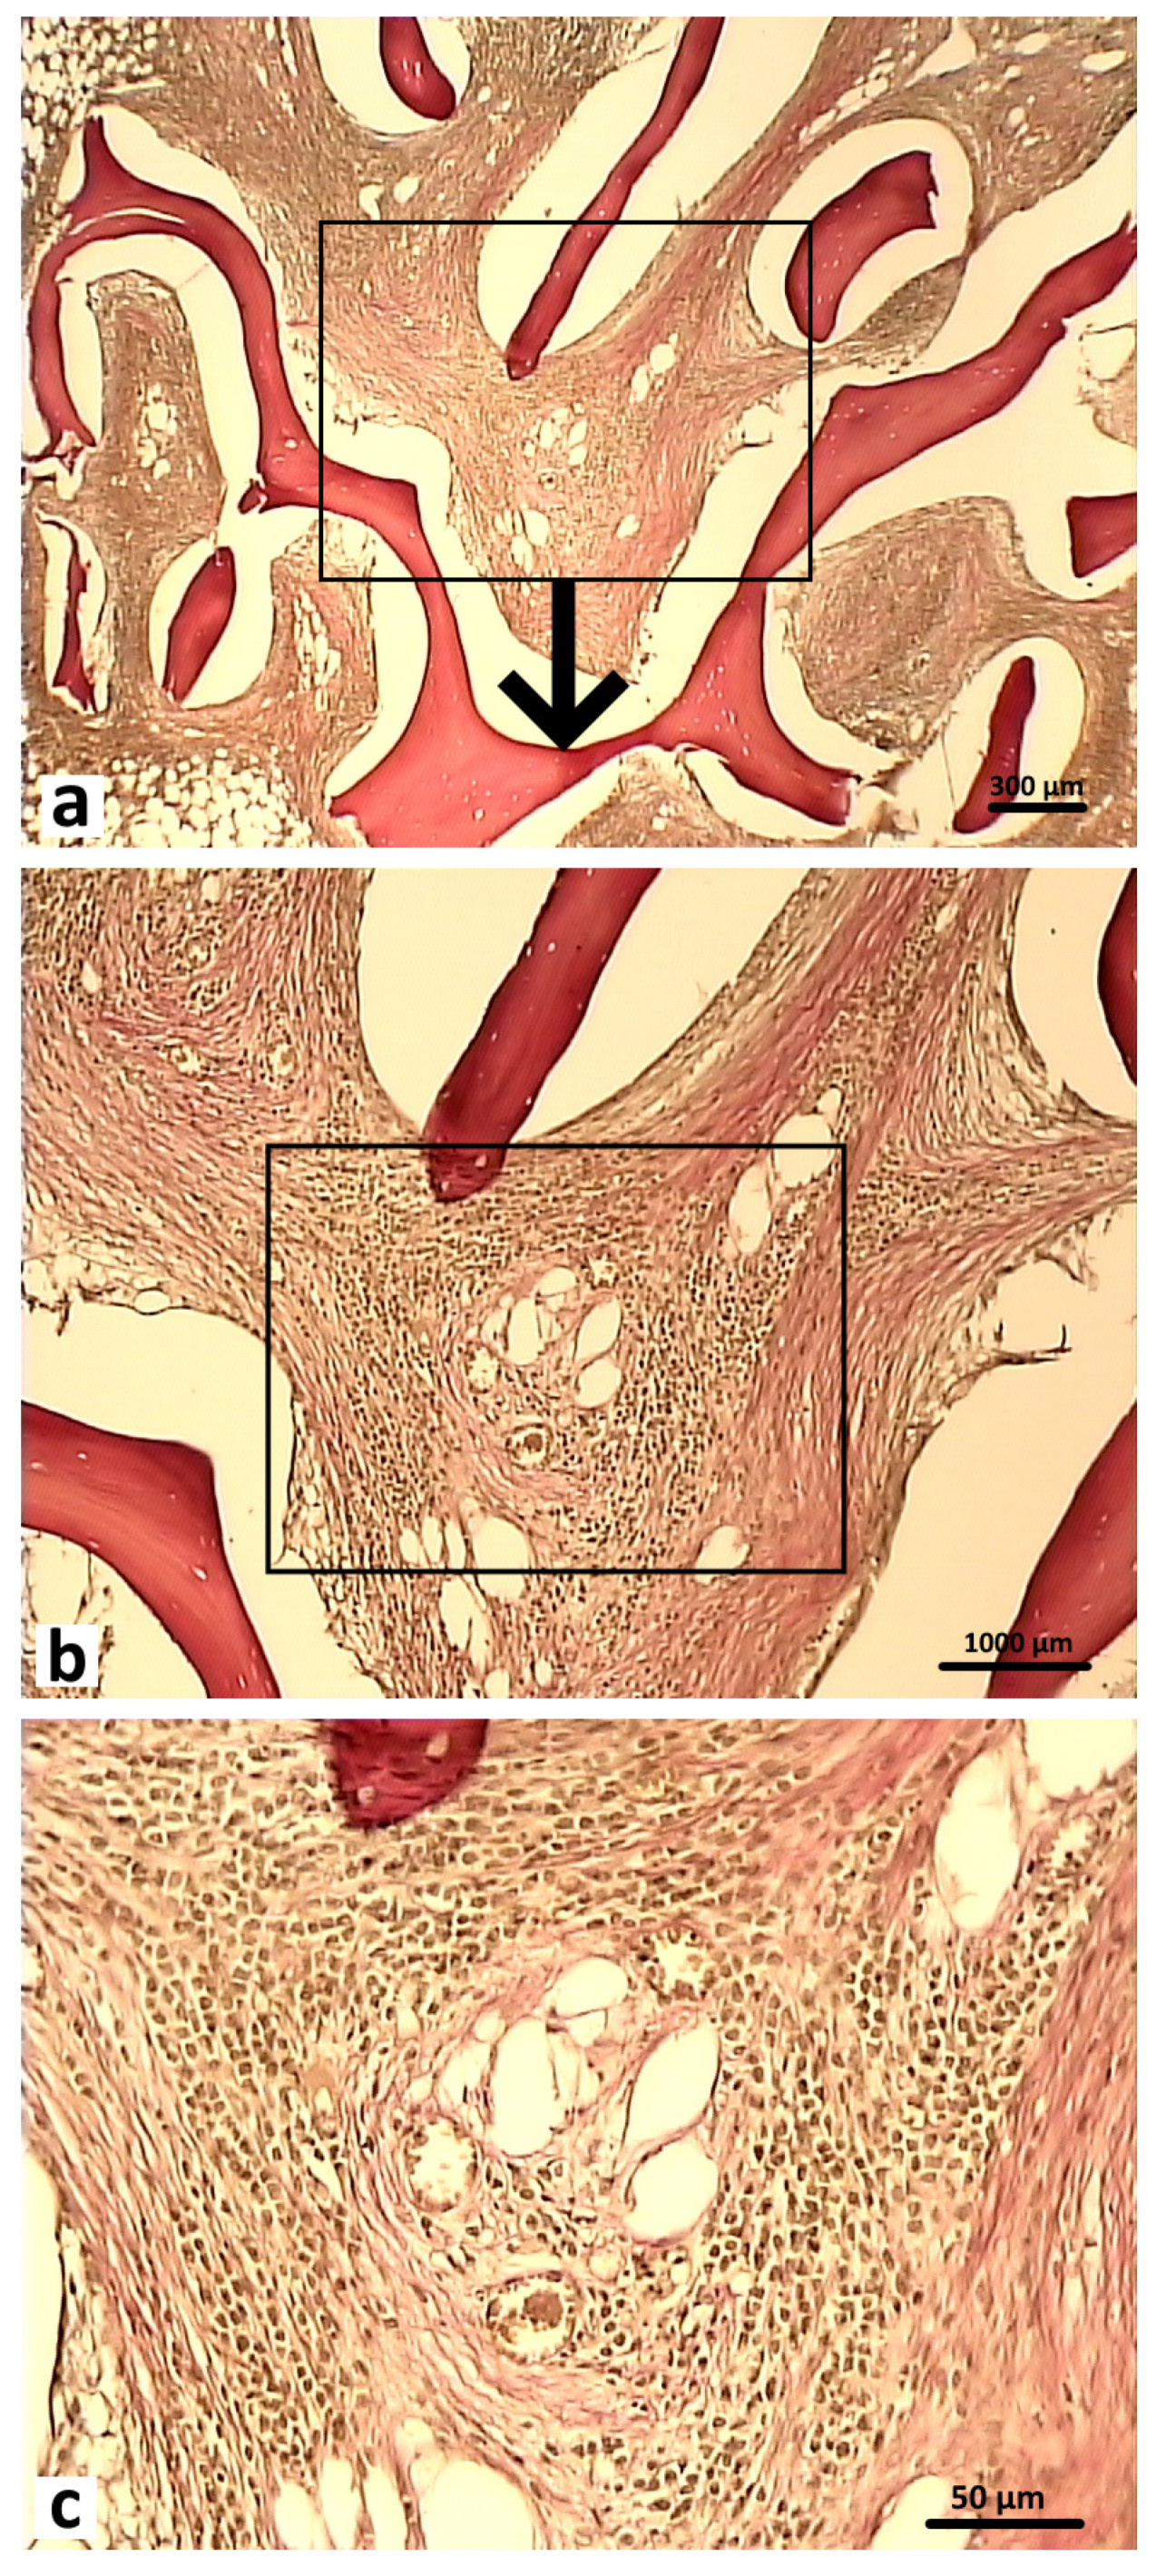

Histological preparations of bone tissue sampled from animals in the experimental group during this observation period showed that the defect was also completely covered by lamellar bone tissue. In the graft localization region, small areas filled with experimental material were found in close contact with heterogeneous groups of cells and microvessels (Figure 16).

Figure 16.

Graft localization area in animals in the experimental group 6 months after surgery (1—hybrid polymer), 1000×: (a) heterogeneous group of cells (indicated by white arrows); (b) microvessels (indicated by black arrows) in close contact with small particles of the hybrid polymer. Hematoxylin and eosin staining.

Therefore, the data obtained in the morphological examination demonstrated that the rate of bone tissue regeneration observed with the hybrid polymer was comparable with the rate observed with the osteoplastic matrix. The results of this long-term investigation enable us to conclude that the graft samples made of hybrid polymer material were safe and biocompatible. Therefore, this material (PHB) can be used to replace bone defects to help optimize osteogenesis in the case of bone tissue damage. It can be assumed that the graft indirectly influences the process of aseptic inflammation in the wound and stimulates the proliferation of osteogenic cells.